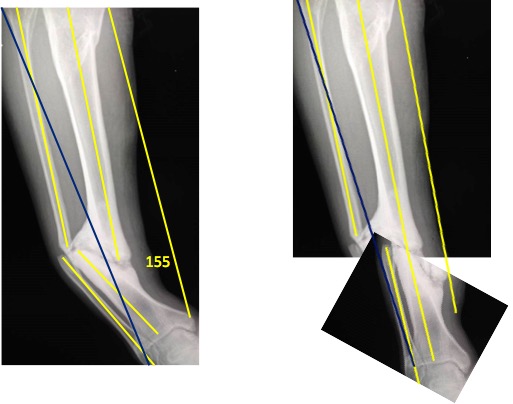

Абсолютно согласен, что с "завязавшим" алкоголиком связываться на

длительное лечение в аппарате очень рискованно. Одномоментная операция

намного надежнее. Во вложении на схемах попытался рассчитать не слишком

ли большое удлинение получится при одномоментной репозиции. Перелом ведь

практически только с угловым смещением. Смещения по длине нет. У меня

получилось, что даже при репозиции стык-в-стык удлинение по наружной

поверхности составит около 8 мм (для пациента ростом около 170 см), а по

внутренней - 24-25 мм. Это не так много. Но ведь пациент уже привык к

укорочению ноги. Если даже голень укоротиться на сантиметр или чуть

больше, пациентом это все равно будет воспринято как удлинение. Думаю,

что при желании в схемах можно будет разобраться. И я полагаю, что

открытая репозиция с удалением избыточной мозоли на наружной поверхности

будет иметь, в данном случае, преимущество. Коррекция в верхней трети

кажется необязательной. Постарался ответить конкретно на поставленные